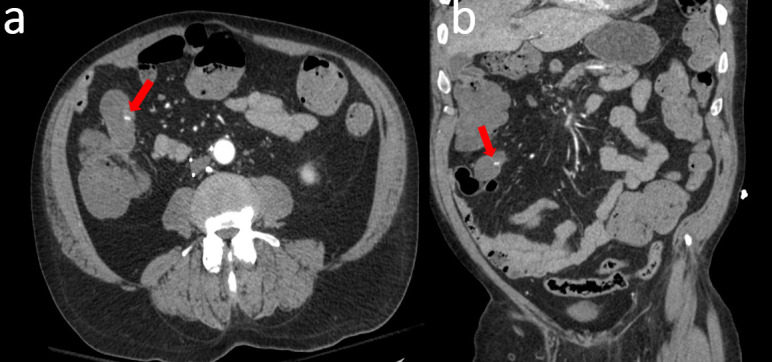

由于梅克尔憩室位置不典型导致大量下消化道出血。

Massive lower gastrointestinal bleeding due to Meckel's diverticulum in an atypical position.